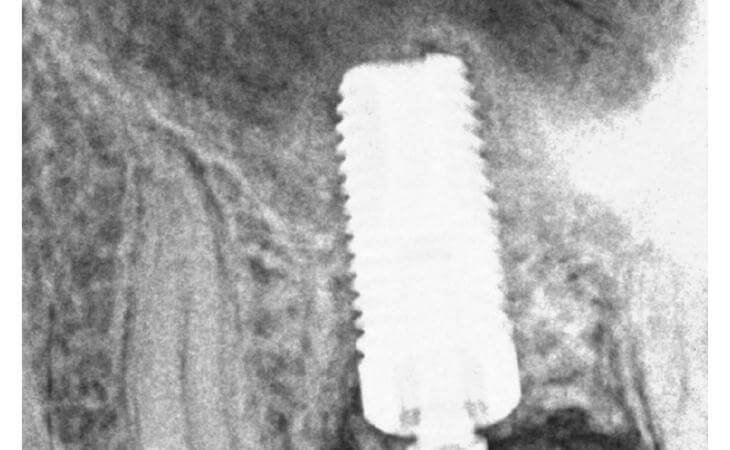

The patient had a decayed molar #14. It was removed and an immediate implant was placed in conjunction with an Internal Sinus lift procedure.

Patient had upper right molar extracted. CT scan revealed insufficient bone volume to place implant as is. Pt underwent INTERNAL SINUS LIFT procedure at the same time as Implant placement. This allowed bone grafting and implant placement to be performed together. State of the Art Surgery

Patient lost upper right molar due to decay. Had insufficient bone for implant placement without a bone graft. Underwent Internal Sinus lIft procedure with Immediate Implant Placement